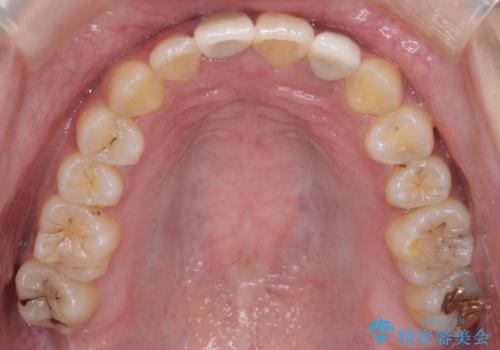

前歯のがたつき 保険治療の前歯の被せ物もやりかえたい

- 前歯のがたつきを主訴に来院。

保険治療の被せ物が前歯に2本あり、矯正治療で移動後にセラミックでやり替えを行っています。

右上のかみ合わせがずれていたため、インプラント矯正を行い、奥歯を後ろに下げて治療しています。